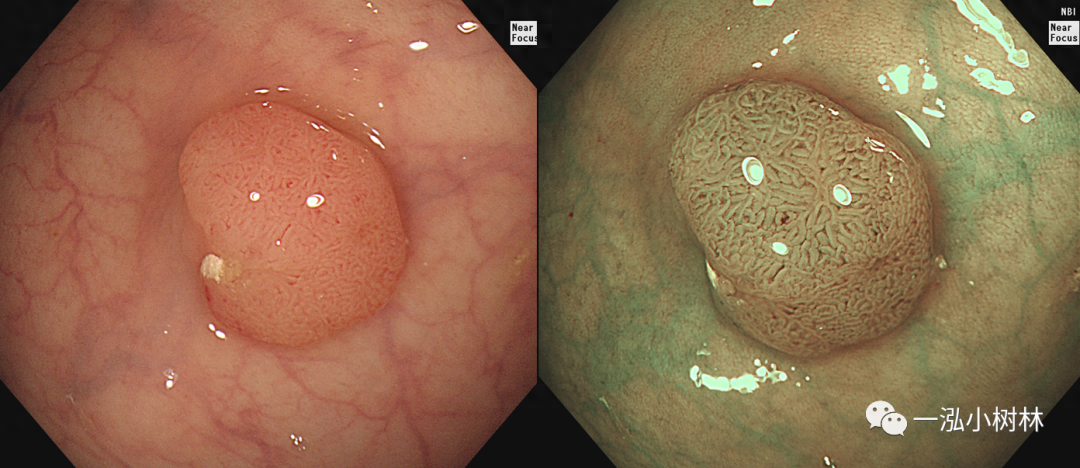

图2 结肠管状腺瘤(Pit Pattern IIIL型)